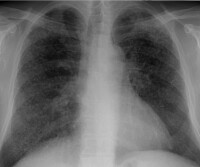

Detaljbilde av en frisk lunge

Lunge uten silikose (detalj)

Detaljbilde av en lunge med silikose

Lunge med silikose (detalj)